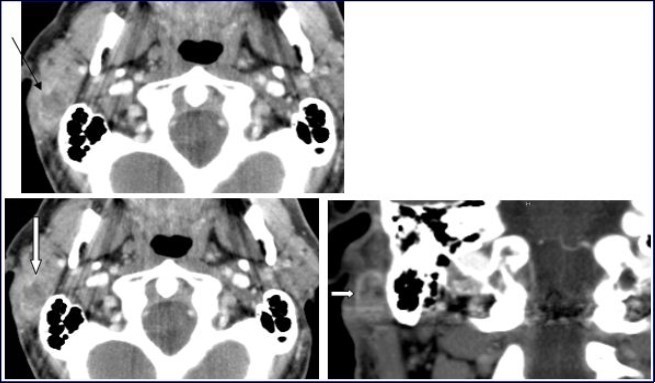

A 54-year-old man consulted for right retro-auricular mass, painless but pruritic, lasting for two months and growing fast. No significant findings in the medical or surgical history. Physical examination revealed a right retro-auricular mass, fixed to the underlying soft tissues measuring 4 x 3 x 3 cm3. The mass had a fluctuating center and there were signs of inflammation around it. Head and neck examination didn’t show any abnormalities or lymphadenopathy. Oto-Rhino-Lyryngologycal and whole-body examinations were unremarkable. Laboratory studies resulted within normal limits. A short course of antibiotic therapy was initially given without any results. Fine needle aspiration (FNA) cytology revealed parotid malignant tumor without precision. The chest-X ray was normal. Head and neck CT with intravenous contrast material showed a focal lesion in the right parotid gland with size 3 × 2 cm2, well-defined, heterogeneous with peripheral contrast enhancement and necrotic center. No evidence of pathologic lymph nodes in or around parotid gland or bony involvement (Figure 1) was found.

Figure 1.Computed Tomography of the neck with intravenous contrast material revealed a focal lesion in the right parotid gland with size 3 × 2-cm. The mass was well defined, heterogeneous, with peripheral contrast enhancement (large white arrow). It had a central attenuation value of 13 HU, suggesting a necrotic mass without bony involvement (thin black arrow).

Computed Tomography of the neck with intravenous contrast material revealed a focal lesion in the right parotid gland with size 3 × 2-cm. The mass was well defined, heterogeneous, with peripheral contrast enhancement (large white arrow). It had a central attenuation value of 13 HU, suggesting a necrotic mass without bony involvement (thin black arrow).